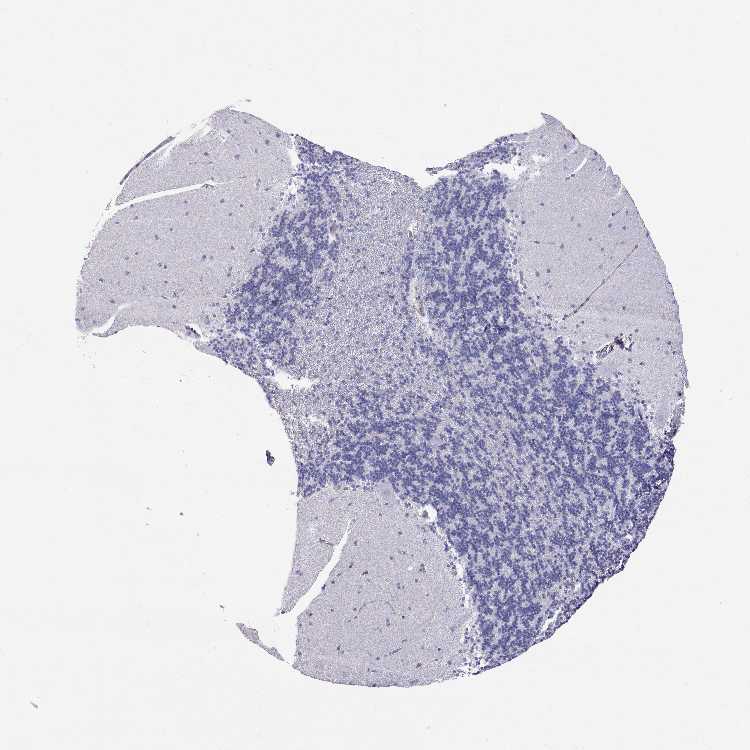

BRAIN CEREBELLUM Show tissue menu

CEREBELLUM - Antibody stainingi

Antibody staining in the annotated cell types in the current human tissue is reported as not detected, low, medium, or high, based on conventional immunohistochemistry profiling in selected tissues. This score is based on the combination of the staining intensity and fraction of stained cells.

Each image is clickable and will lead to virtual microscopy that enables deeper exploration of all samples and also displays staining intensity scores, fraction scores and subcellular localization as well as patient and tissue information for each sample.

Antibody HPA065711

Purkinje cells Not detected

Cells in granular layer Not detected

Cells in molecular layer Not detected